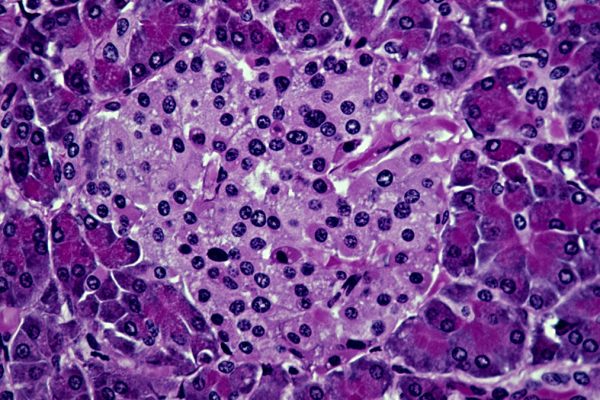

Ceea ce face noul abordare să se remarce este faptul că reușește să combine cu succes celulele sistemului imunitar atât de la șoarecele pacient, cât și de la un șoarece donator, încurajându-le să trăiască în armonie fără a fi nevoie de medicamente imunosupresoare timp de cel puțin patru luni. Cercetătorii din spatele acestui studiu, coordonați…